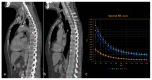

Dual-energy computed tomography (DECT) is one of the most promising technological innovations made in the field of imaging in recent years. Thanks to its ability to provide quantitative and reproducible data, and to improve radiologists' confidence, especially in the less experienced, its applications are increasing in number and variety. In thoracic diseases, DECT is able to provide well-known benefits, although many recent articles have sought to investigate new perspectives. This narrative review aims to provide the reader with an overview of the applications and advantages of DECT in thoracic diseases, focusing on the most recent innovations. The research process was conducted on the databases of Pubmed and Cochrane. The article is organized according to the anatomical district: the review will focus on pleural, lung parenchymal, breast, mediastinal, lymph nodes, vascular and skeletal applications of DECT. In conclusion, considering the new potential applications and the evidence reported in the latest papers, DECT is progressively entering the daily practice of radiologists, and by reading this simple narrative review, every radiologist will know the state of the art of DECT in thoracic diseases.